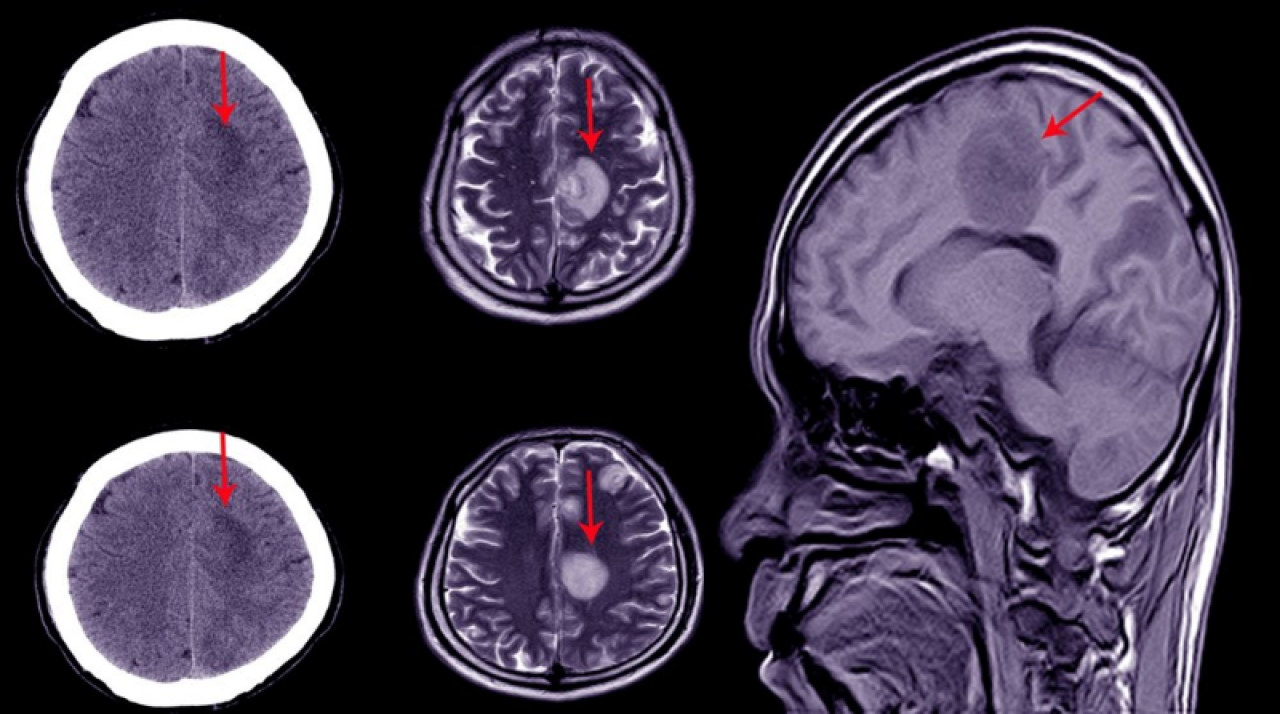

Beyninin yüzde 90'ı eksik olmasına rağmen nispeten normal ve sağlıklı bir hayat yaşayan bir adam, bilim dünyasını şaşkına çevirdi. Bu durum beyin ve bilinç hakkında mevcut anlayışların sorgulanmasıyla bilim dünyasında geniş bir etki yarattı.

Yıllar önce kimliği bilinmeyen Fransız bir adamın beyninin yüzde 90'ının eksik olduğu ancak normal bir yaşam sürdüğü tespit edildi.

Bu durum, beyin ve insan bilinci hakkında var olan bilgileri yeniden sorgulamaya yol açtı.

KAFATASI SIVI İLE DOLU

2007 yılında The Lancet dergisinde yayımlanan bu hikaye, bilim dünyasında büyük bir yankı uyandırdı.

44 yaşındaki adam bacağında güçsüzlük hissi yaşaması üzerine doktora gitti. Yapılan muayenede, beyninin büyük bir kısmının kayıp olduğu ve kafatasının sıvı ile dolu olduğu belirlendi. Bu durum hidrosefali olarak biliniyor.

Çocukken bir stentle tedavi edilen adamın, stent çıkarıldıktan sonra beyninin büyük kısmı aşınmıştı. Beyin taramalarında, beyin dokusunun büyük kısmının sıvı ile dolduğu ve tahrip olduğu gözlemlendi.